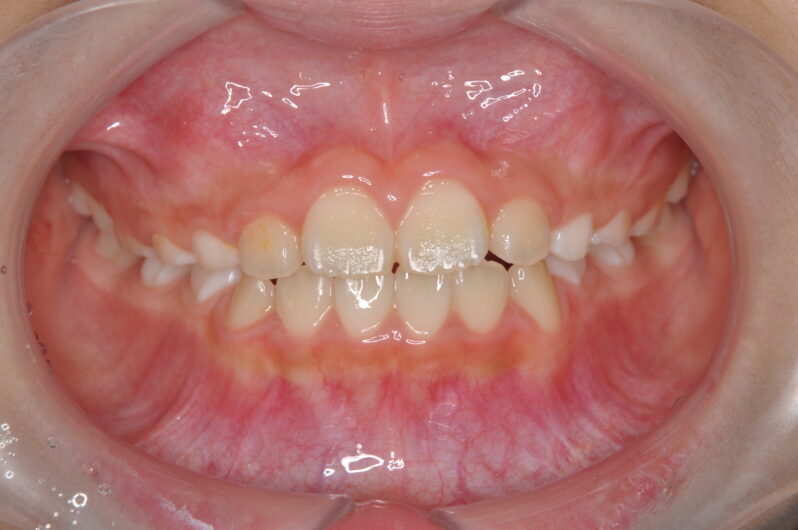

反対咬合の改善後は、仕上げとしてマウスピース型の装置へ移行。

この後、マウスピースに移行